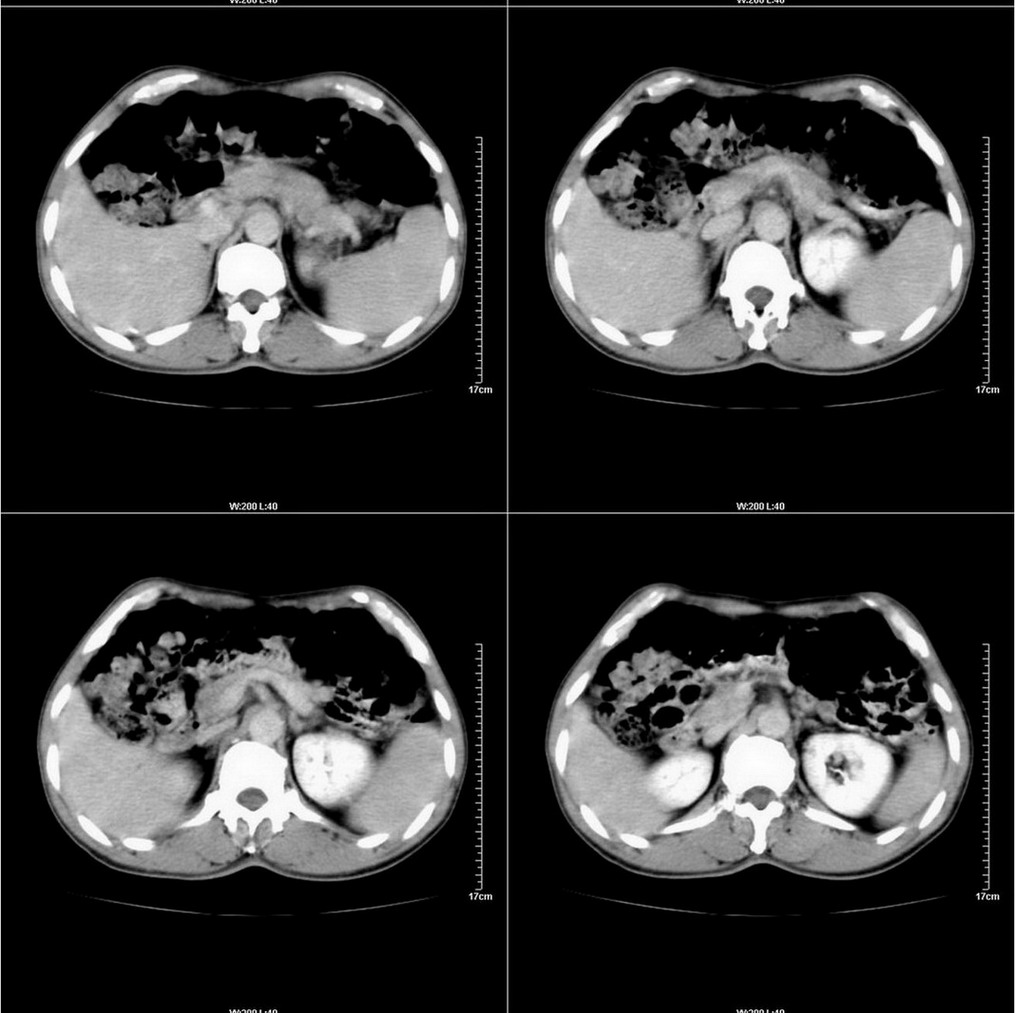

标题: CT14220:男性,59岁。腹部疼痛不适半年余。 [打印本页]

标题: CT14220:男性,59岁。腹部疼痛不适半年余。

建议结合胃镜或钡餐检查,考虑胃底贲门癌可能性大。

肝右叶5段小囊肿。

考虑:1、肝右叶下部小囊肿;

2、胃可能为准备充盈不良所致,必要时请胃镜进一步检查。